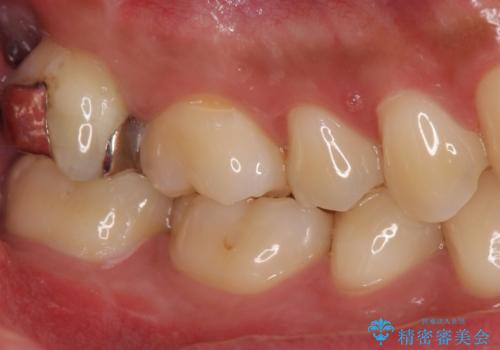

銀歯をなくしたい ジルコニアクラウンでの修復

歯を覆っている銀の詰め物の面積が広く、セラミックで同じ形態にすると強度に不安が残るため被せ物での修復処置を行っていきます。

ブラッシングが上手な患者様であったため歯茎の締りもよく、大変適合の良い被せ物を装着することができました。